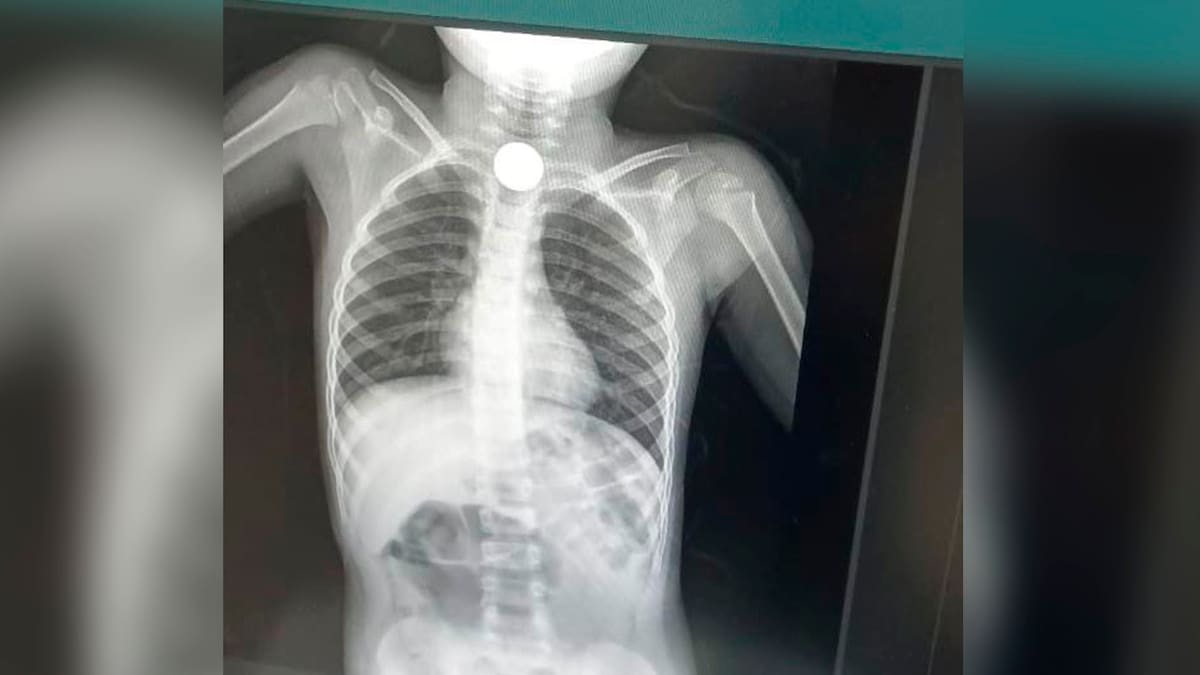

Dos días tuvo que esperar un niño de 6 años identificado como Keiner López para que finalmente le extrajeran dos monedas que se tragó, en hechos ocurridos en el corregimiento de Palmor de la Sierra, en el área rural del municipio de Ciénaga, Magdalena.

El menor fue remitido hasta el hospital San Cristóbal de Ciénaga, allí le realizaron una placa y efectivamente tenía la moneda atorada en la garganta.

Al no contar con especialistas para este procedimiento, lo trasladaron a la clínica Mar Caribe, en Santa Marta, donde tampoco pudieron solucionar el problema y lo remitieron a la clínica Cehoca de la misma capital, donde finalmente tras los estudios adecuados lograron extraerle los objetos metálicos, que ponían en riesgo su salud.